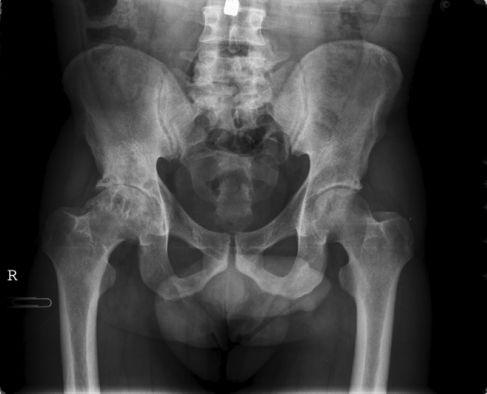

La necrosis aséptica de la cadera es la muerte de tejido óseo en la cabeza del fémur a causa de un abastecimiento inadecuado de sangre.

Algunos huesos tienen un frágil abastecimiento de sangre. La cabeza del fémur en la articulación de la cadera es más propensa a sufrir pérdida de abastecimiento de sangre y consiguiente muerte de tejido. Si no se identifica ni se corrige, progresará hasta generar una deformidad y causar dolor y renquera.

- Radiografía: prueba que emite radiación para generar una imagen de las estructuras internas del cuerpo, especialmente de los huesos. Cuando la enfermedad se observa en una radiografía, generalmente está demasiado avanzada como para revertirla con un tratamiento.